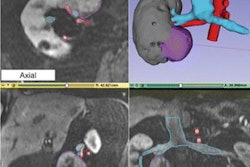

Following acquisition, images are segmented using the Mimics software (Materialise) to delineate the appropriate anatomical regions of interest (ROIs) to be included in the AR visualization. Next, computer-aided design modeling is performed. Each ROI is converted to a 3D surface "mesh," which is then exported in the STL file format -- the most common format used for 3D printing, according to the researchers.

The 3-matic software (Materialise) is then used to perform "marginal local smoothing" to minimize the pixelated appearance of the images. In addition, contours are created and overlaid onto the DICOM images. This ensures that the models accurately reflect the anatomy and that all anatomical structures can be viewed simultaneously in 3D, according to the researchers.